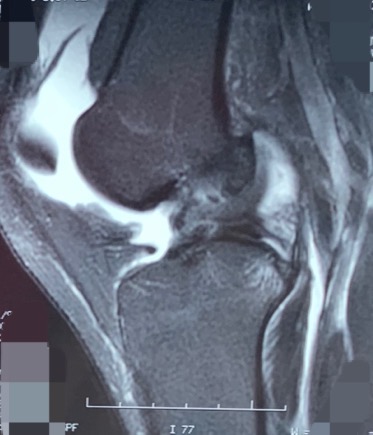

以下是他的磁共振

红色指的地方就是半月板后角损伤的地方

左膝是半年前踢球时扭到了,随后出现打软腿,上下楼梯时发力都发不了。我查体一看,前后稳定性非常明显的不稳,前抽屉试验阳性的,看了磁共振,明显的前十字韧带断裂了。

前十字韧带断裂明显